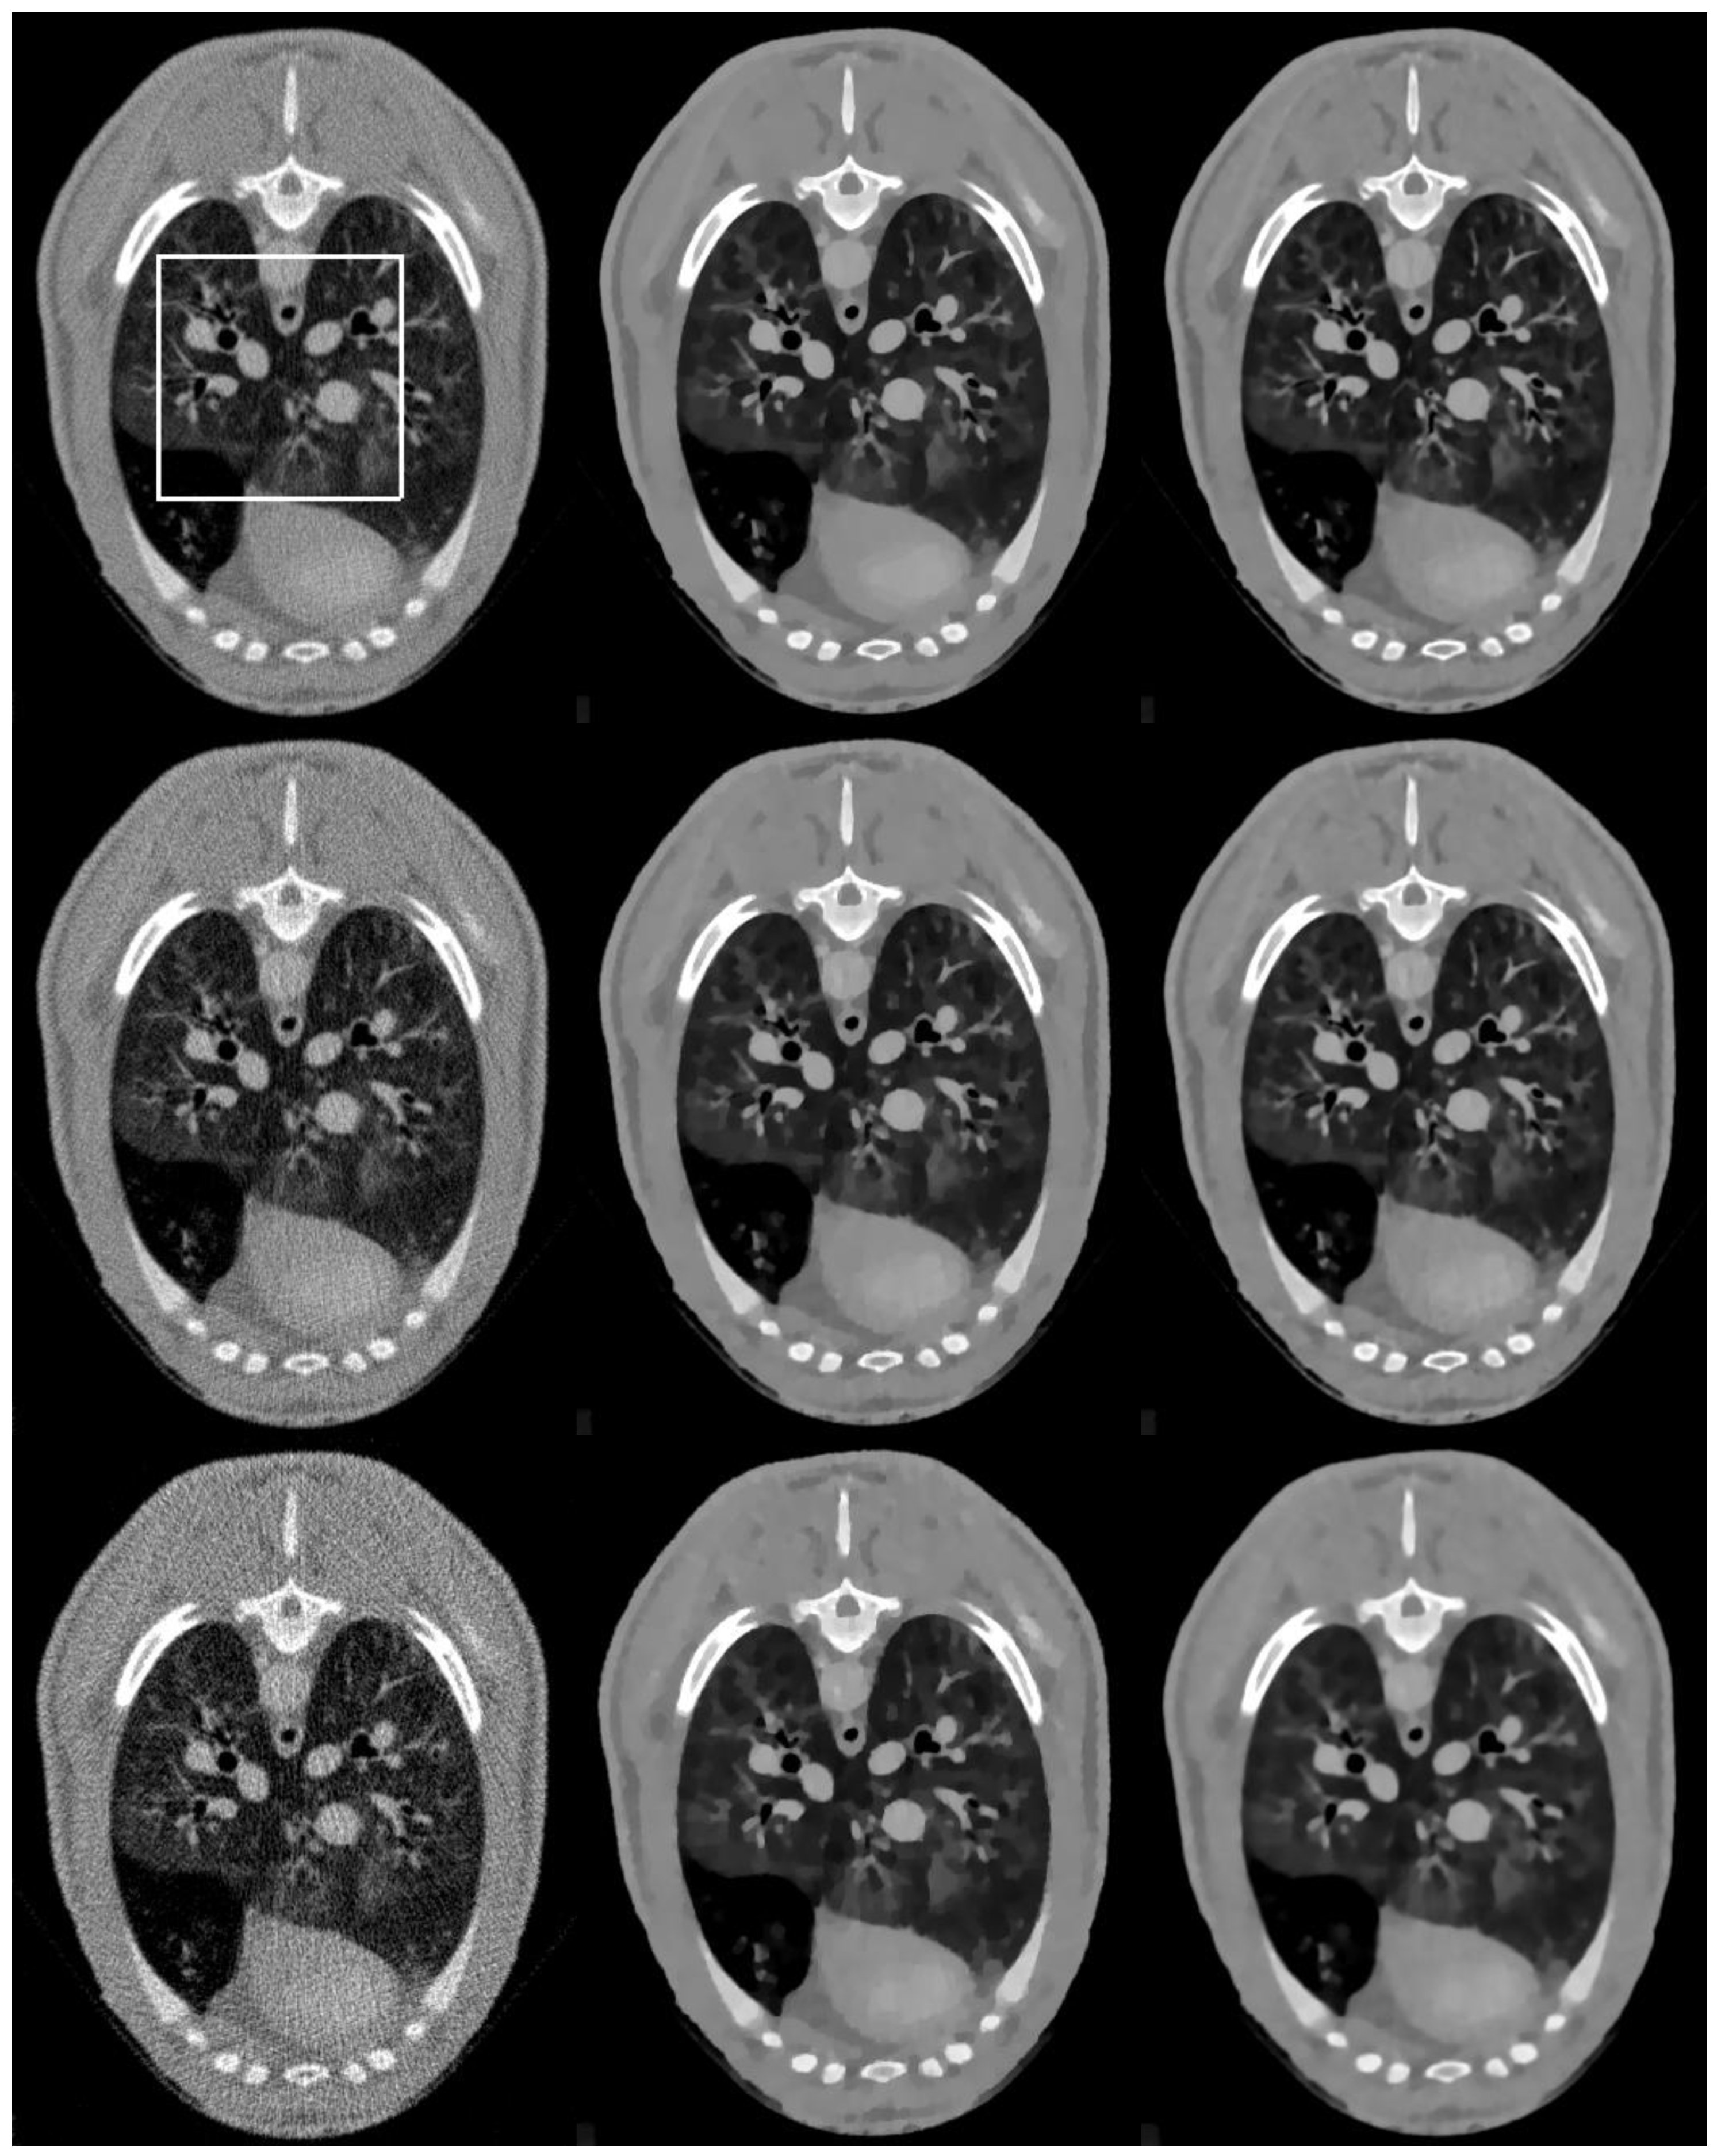

3.1.2. Visual Quality Comparison

Figure 3 shows the reconstructed brain images and zoomed regions of interest(ROI) (indicated by the red square in Figure 1a) reconstructed from low dose projections. Images in the left, middle, and right column are reconstructed by the FBP, SIR-TV, and SIR-STV1 method, respectively. Images in the first, second, and third row are reconstructed from noisy projections with incident photon numbers 5 × 103, 1 × 104, and 5 × 104, respectively. In the SIR-STV1 method, parameters σ and L K are selected according to the method described in Ref. [21], i.e., σ = 0.5 , L K = 3 , the number of subset were set to 40. For the reconstruction from noisy projections with incident photon numbers 5 × 103, 1 × 104, and 5 × 104, the parameter λ were set as 6 × 10−5, 2 × 10−5, and 9 × 10−6, respectively. It can be seen that the FBP results contains serious noise, and became worse and worse when the number of photon decreased from 5 × 104 to 5 × 103. The SIR-TV method removes noise but the reconstructed image suffers from over smoothing effect. The reconstructed results using the SIR-STV1 perform better in restraining the blocky effect and removing image noise than other methods, and are almost visually the same as the original image.

Figure 3. Images reconstructed by the FBP (left column), SIR-TV (middle column), and structure tensor total variation SIR-STV1 (right column) methods from noisy projections with incident photon numbers 5 × 103 (the first row), 1 × 104 (the second row), and 5 × 104 (the third row). The display window is [−1000, 667] HU.